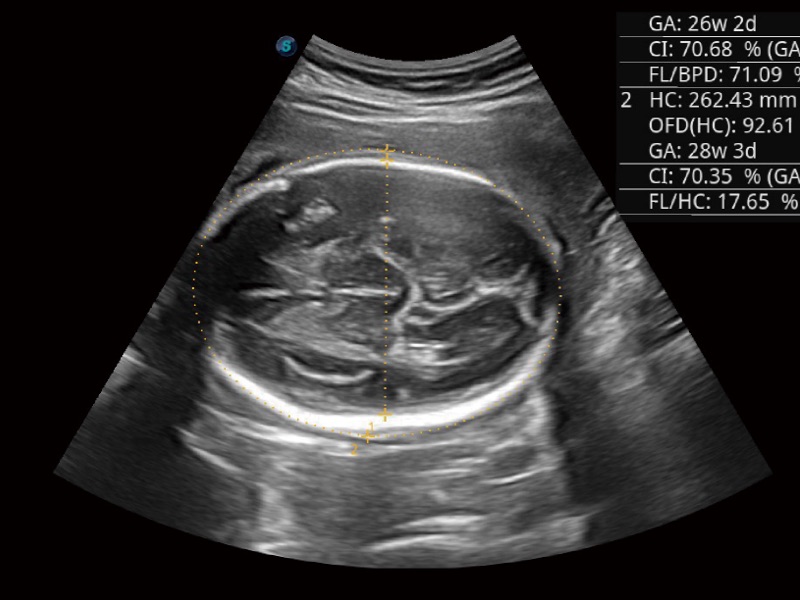

妇产科应用

宽频带及多频段变频结合开立频率复合技术,使得每一支探头可以很好地给临床带来穿透力与分辨率的完美结合,图像真实,提供临床诊断准确性。